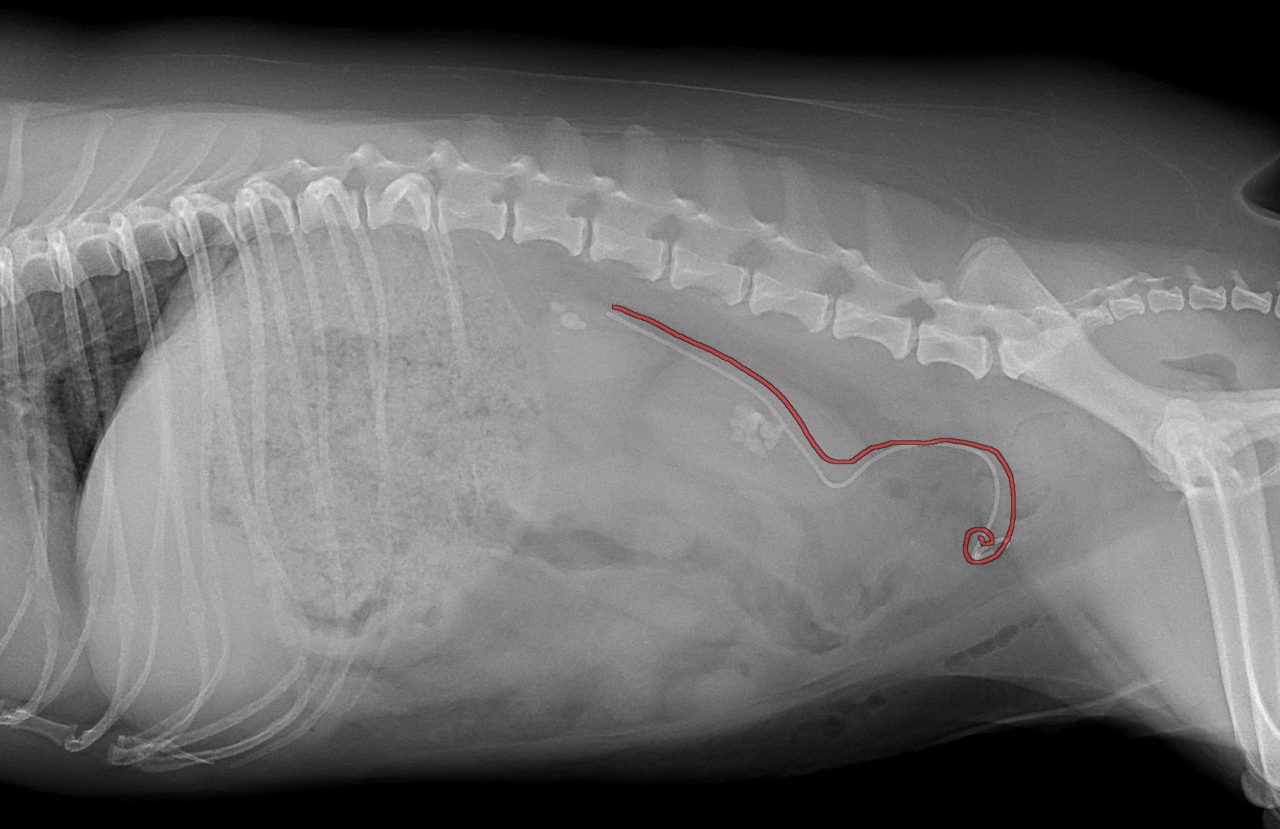

かかりつけ医で定期的に超音波検査で腎結石のモニターをしていたところ、急に腎盂が拡張してきたので早急に対応して欲しいと連絡がありました。尿管結石により尿路閉塞が起こっていました。マイクロサージェリーで尿管を2箇所切開し、尿管結石を摘除しました。術後の狭窄予防に一時的に尿管ステントを留置しています。術後翌日から、腎盂拡張は解消しましたが、術後の経過により、生体にとって異物となる尿管ステントは抜去する予定です。